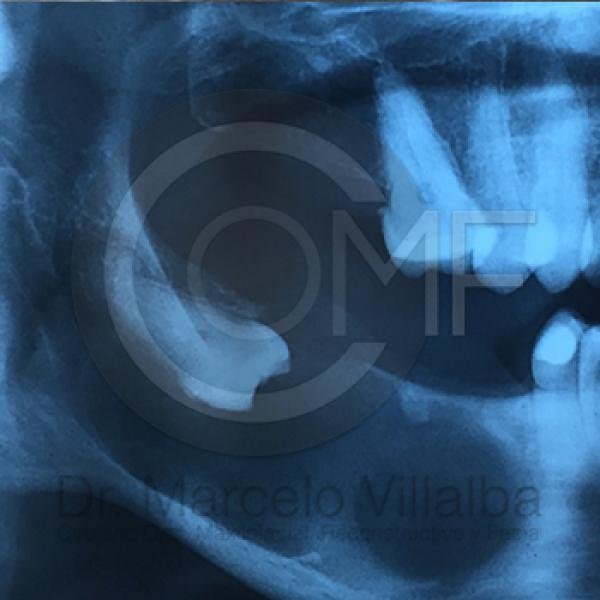

Contenido Sensible y Gráfico

Si usted no pertenece al área de la salud, las imágenes pueden ser muy explícitas.